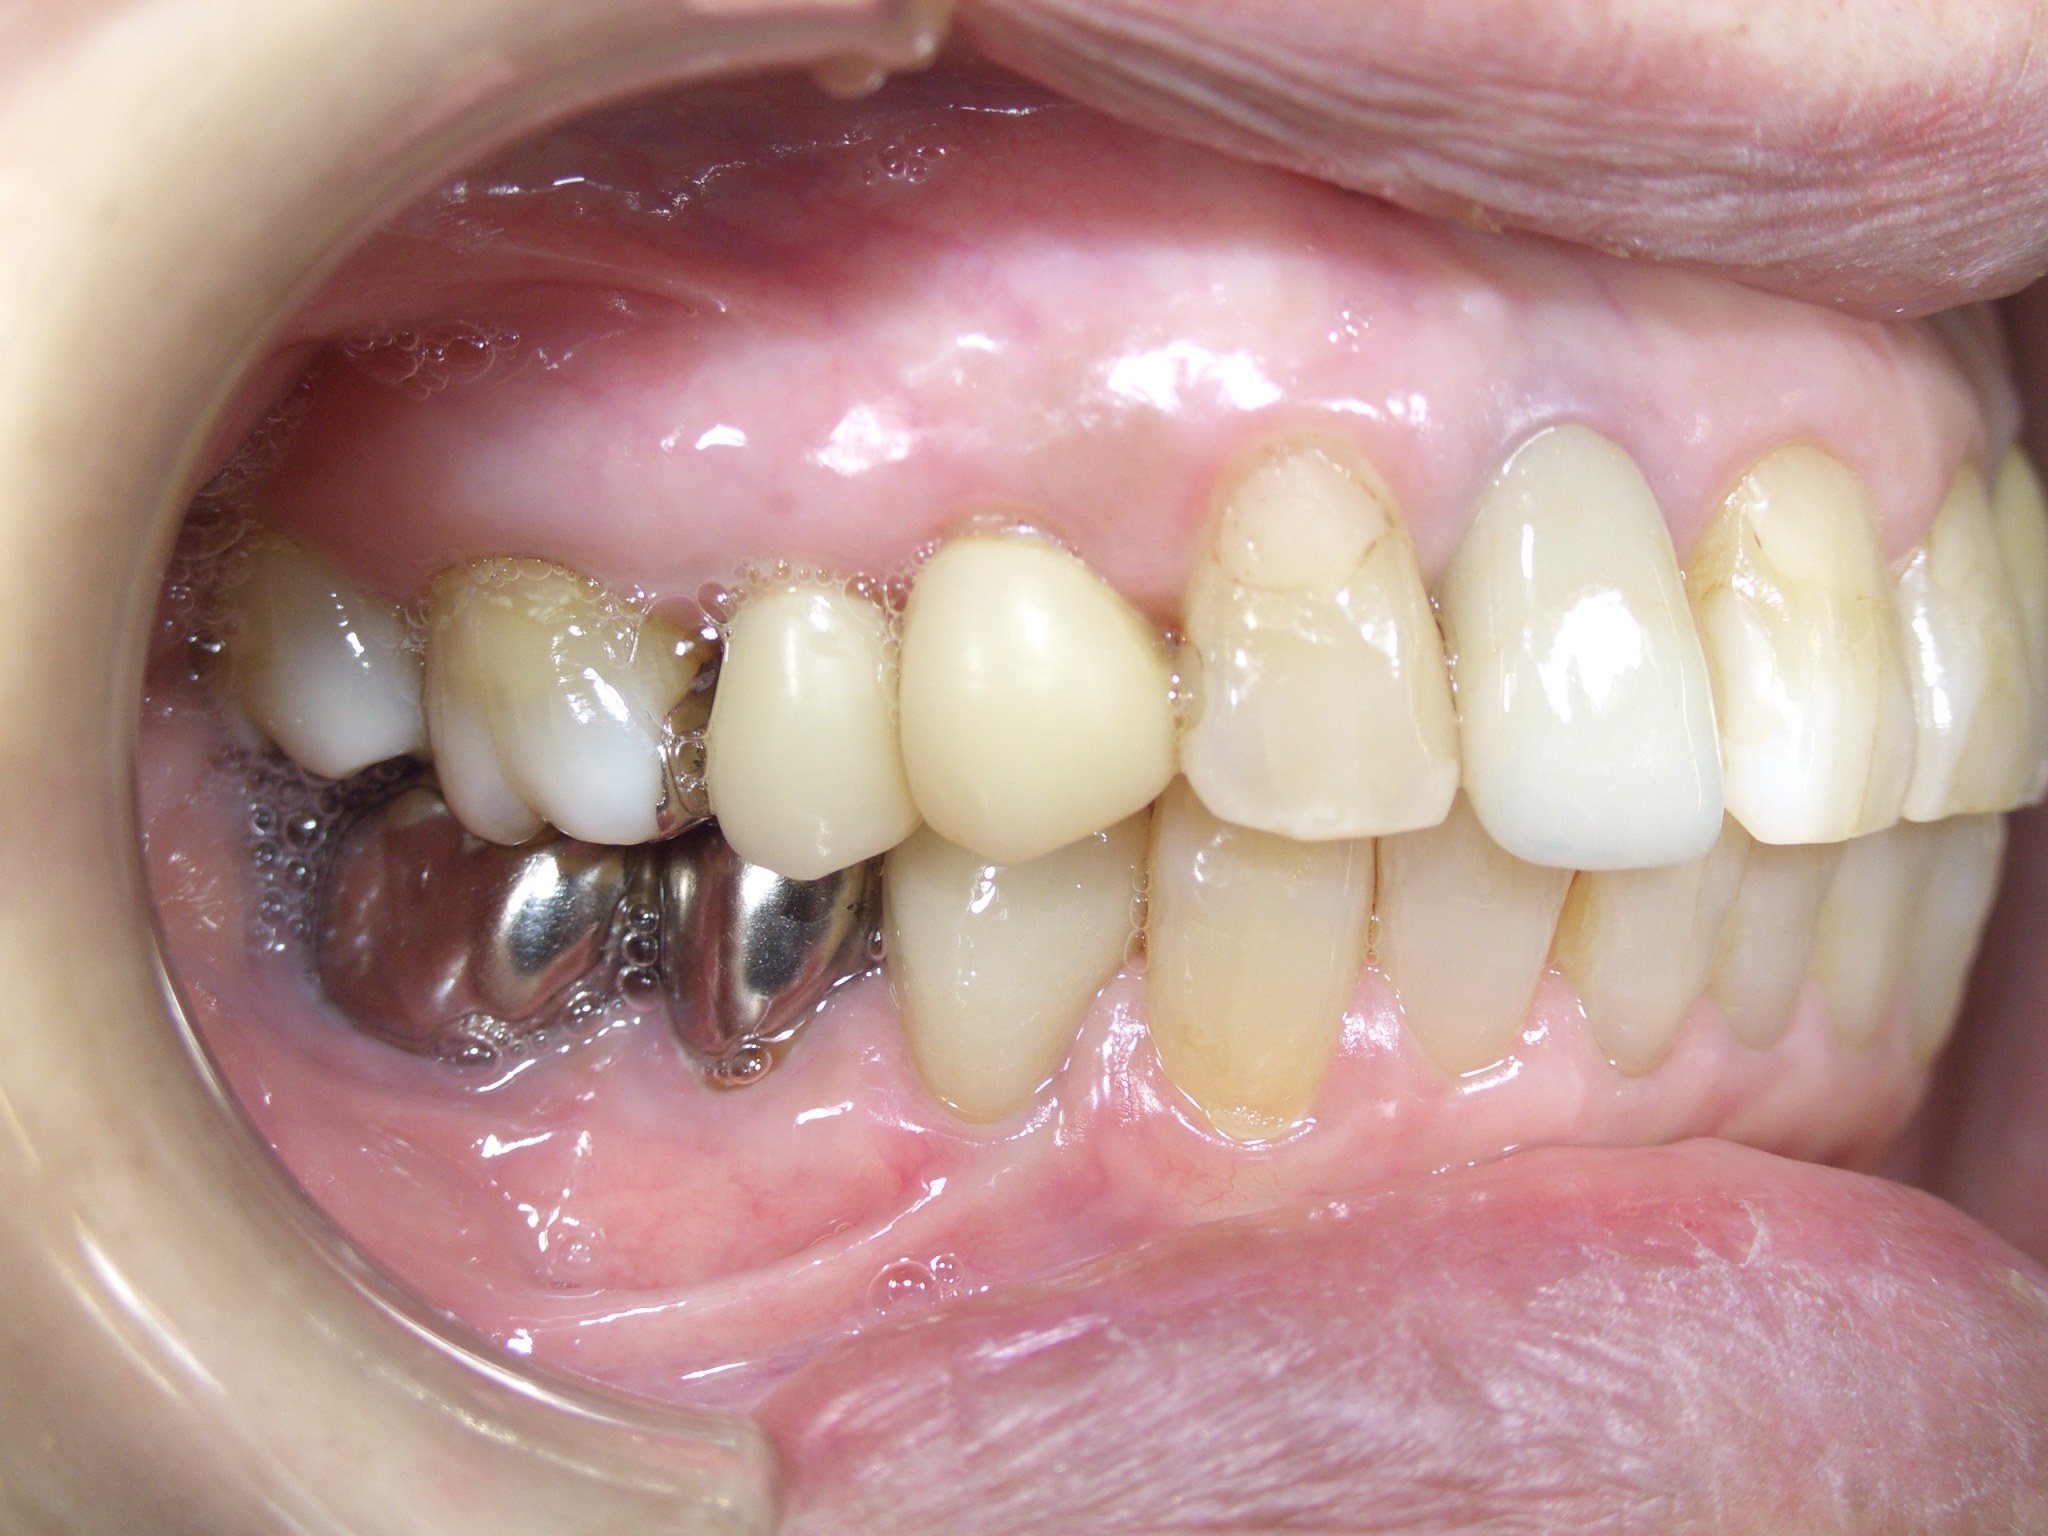

治療前

以前治療した歯の状態が悪くなり、当院を調べて来院されました。

インプラントを行った部位の歯は、神経の処置がしてあり、痛みはありませんでしが、2次虫歯が酷く、また骨(歯槽骨)が破壊されており、残念ながら抜歯を行いました。

骨の状態も悪く、そのままではインプラントが埋入できなかったので、GBR(骨を造る処置)を行って埋入しています。

インプラントの手前の歯は、根管治療を行いセラミックの被せ物をしました。

奥の歯2本は、それぞれ2次虫歯でしたが、神経は感染していなかったので、健康なエナメル質は温存して、セラミックとジルコニアで治療を行いました。